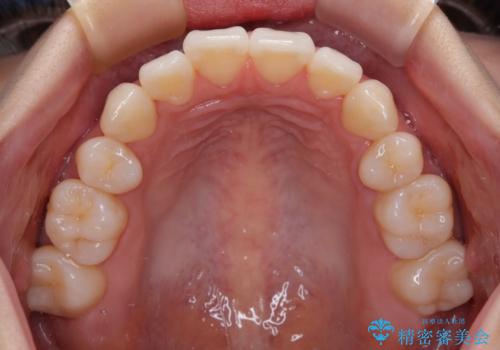

1. 抜歯矯正の軽度後戻りを解消 インビザライン矯正の治療前

2.

3. 抜歯矯正の軽度後戻りを解消 インビザライン矯正の治療後